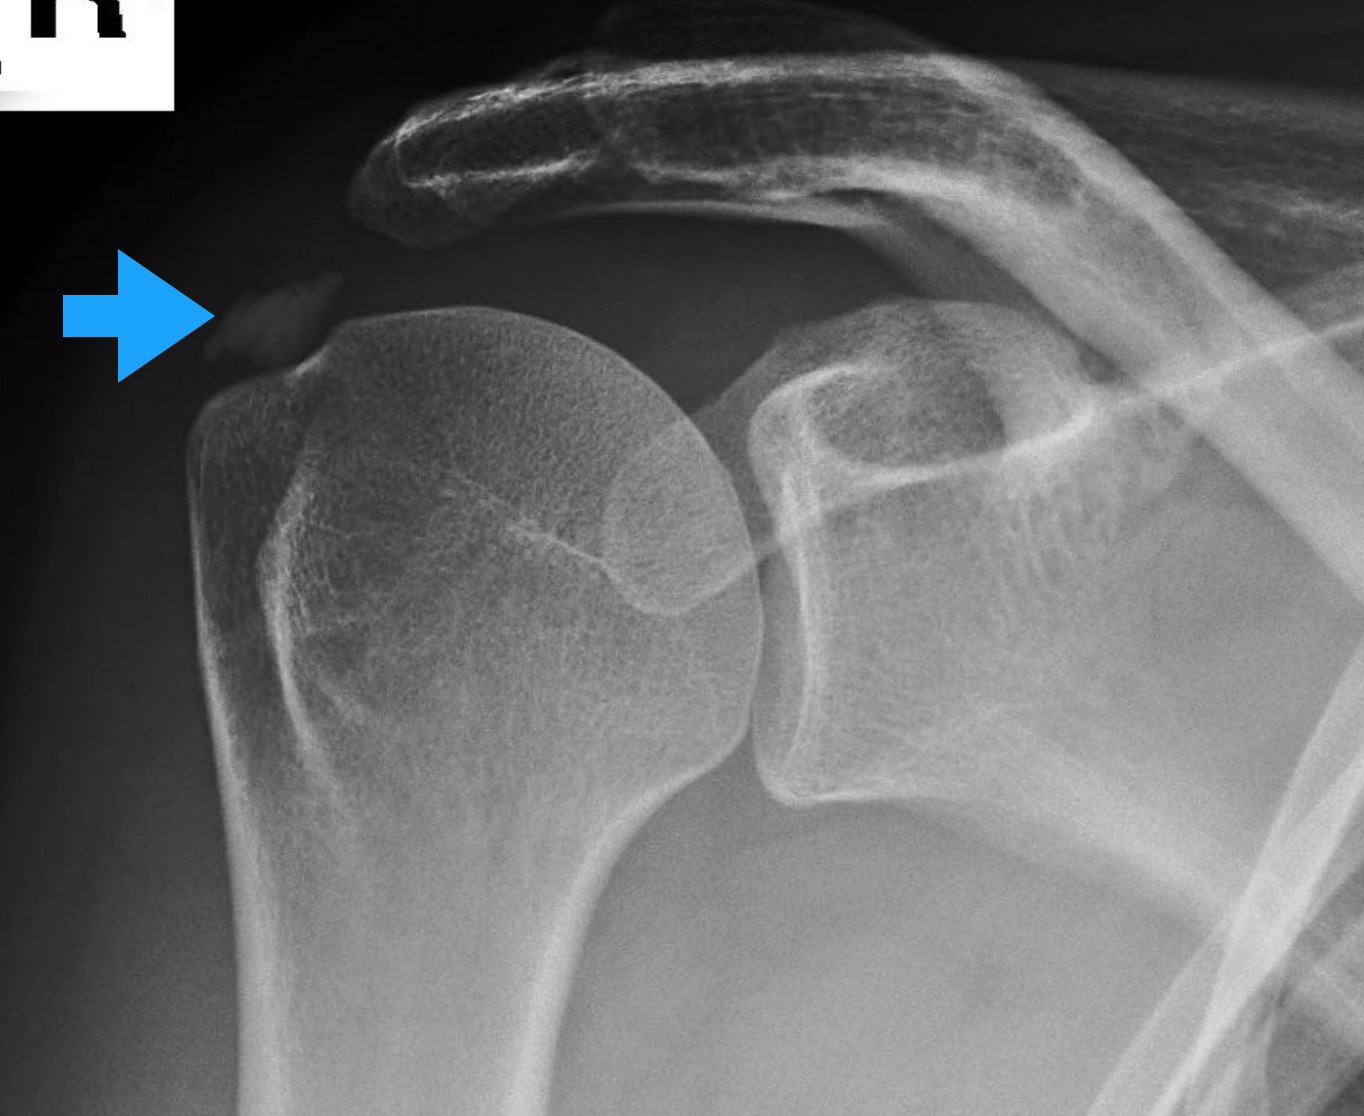

| Fase Clínica | Sintomas Típicos | Aparência no Raio-X |

| Fase Formativa | Dor leve a moderada, piora com esforço. Sensação de “pinçamento”. | Depósito denso, bem definido, homogêneo. |

| Fase de Repouso | Pode ser indolor ou causar desconforto mecânico se o depósito for grande. | Calcificação bem delimitada, aspecto de “giz”. |

| Fase de Reabsorção | Dor Aguda Incapacitante. Início súbito, sem trauma. | Depósito “nublado”, bordas mal definidas, aspecto de “nuvem”. |

- Radiografia (Raio-X): É o melhor exame para ver o cálcio. Permite classificar a fase da doença (Gärtner) baseada na densidade do depósito.